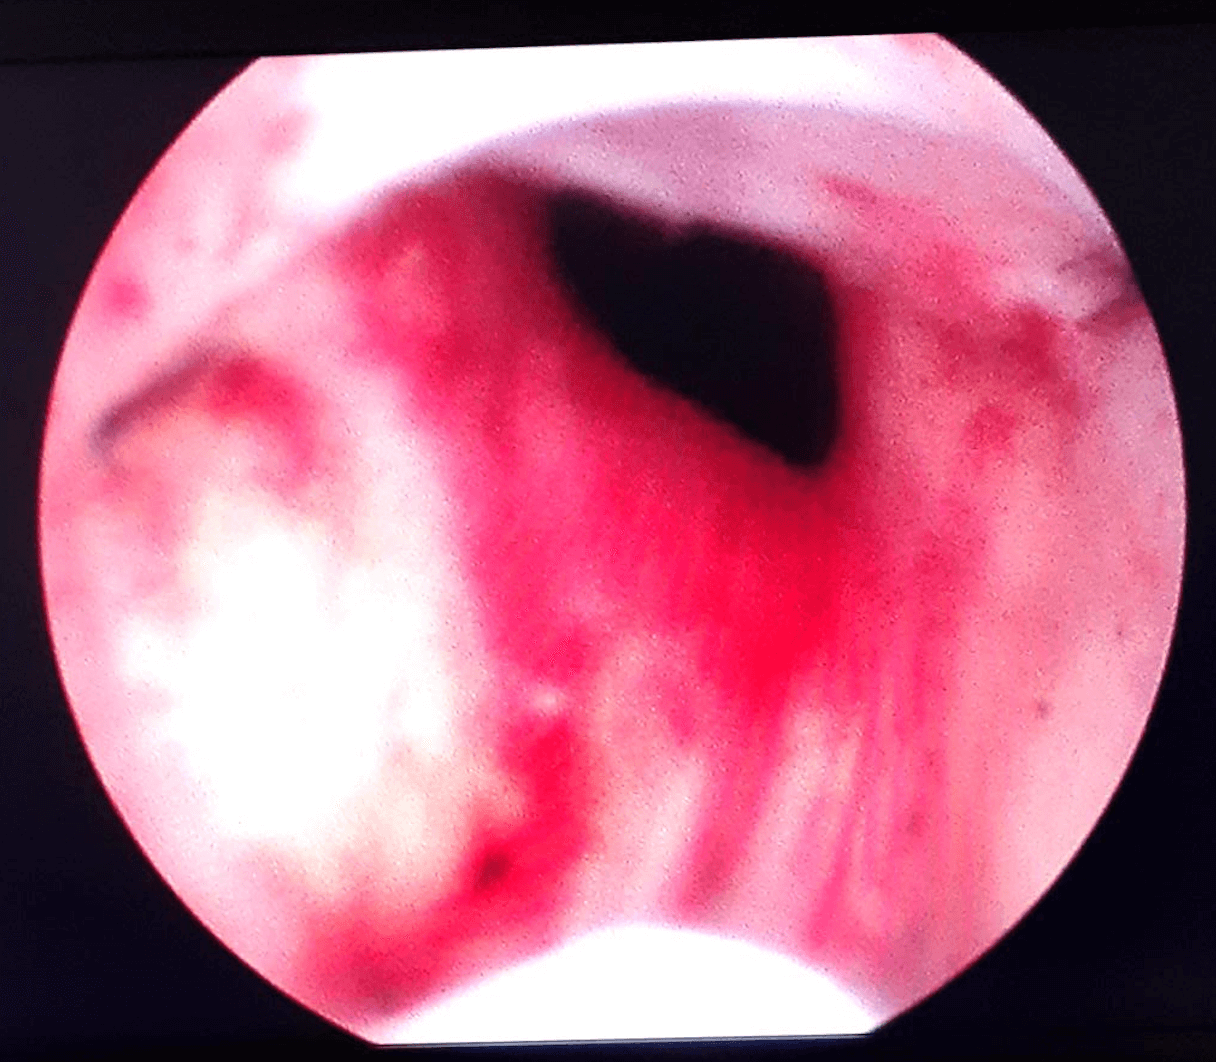

Before & After Pics of UroLift in Atlanta

Procedure